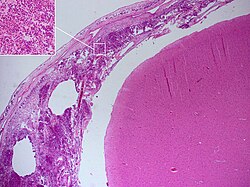

Meningitis se može dijagnosticirati i nakon smrti. Na obdukciji se obično nalazi opsežna upala meke moždane ovojnice (Pie mater) i paučinaste moždane ovojnice (Arachnoidee). Neutrofilni granulociti koji su dospjeli u cerebrospinalnu tekućinu i na bazu mozga, okružuju i moždane živce i kralježničku moždinu, koji mogu biti okruženi gnojem — kao i krvne žile u moždanim ovojnicama.[35]